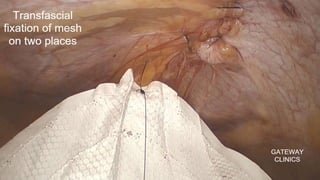

STEP 5: Deploying and Anchoring the Mesh

• A large (15x12 cm) polypropylene mesh.

• The mesh is inserted from the Camera trocar. Then, the mesh is

placed in the appropriate position and fixed by 1 Polypropylene

sutures (or tacking staples, glue in some centres). The first suture is at

the level of pubis

• The mesh is fixed on the upper and internal edge

• The mesh shouldn’t be sutured/stapled at the level of dangerous

triangles and epigastric vessels